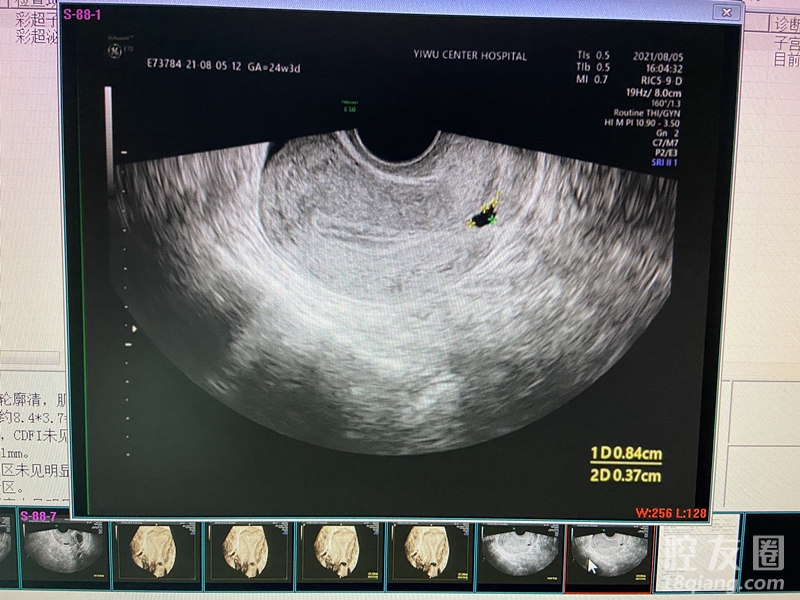

今年,夫妻俩决定要个二胎,可备孕很久都没怀上,佳佳这才这才想着上医院做个检查。在中心医院妇科专家门诊,佳佳的三维B超检查提示“子宫前壁下段疤痕处暗区(憩室考虑)”。

剖宫产术后子宫疤痕憩室,是指剖宫产术后子宫切口愈合不良,子宫瘢痕处肌层变薄,形成一与宫腔相通的凹陷或腔隙。

施宝美介绍,对于子宫疤痕憩室的诊断,医生将根据患者病史、症状及影像学检查进行综合判断,目前主要有药物治疗和手术治疗两种。对于有相应的临床症状、影响患者生命质量、患者有治疗需求的,建议手术治疗。当然,子宫疤痕憩室的手术治疗有其相应的适应症。